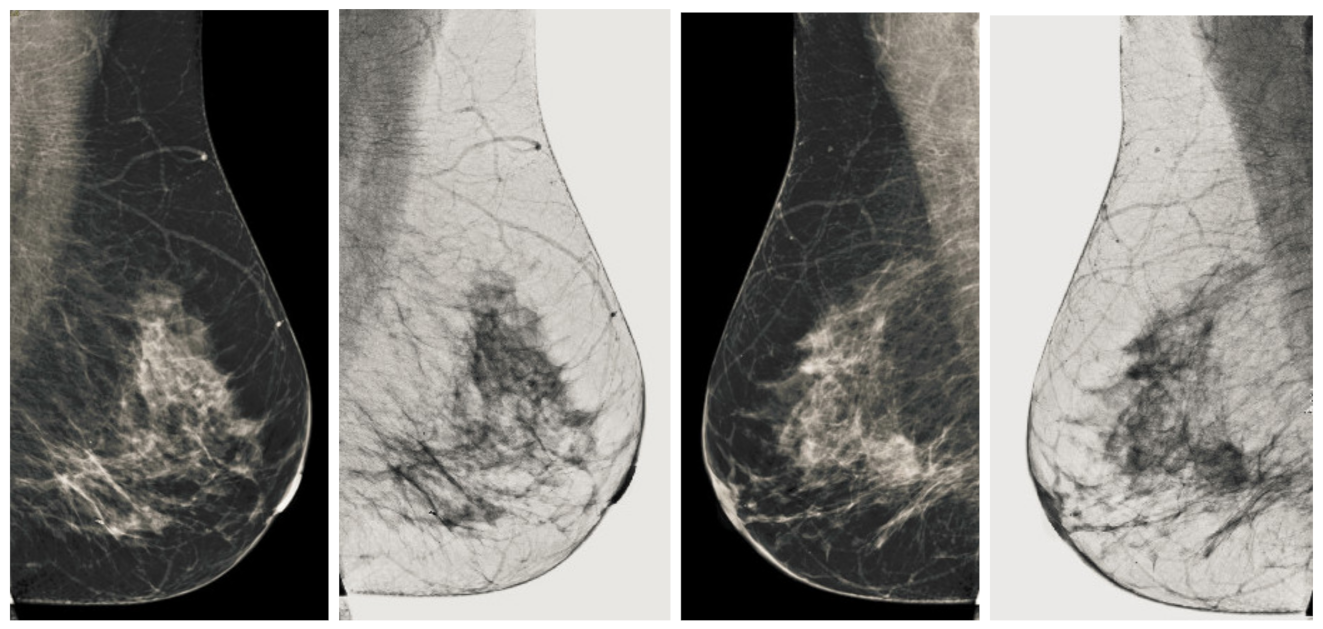

Figure 7.

Analysis of CC view of BI-RADS-1 mammogram images.

Figure 8.

Analysis of MLO view of BI-RADS-1 mammogram images.

We also measured the PSNR, the image contrast, and the EME of each category of databases, as we analyzed the image in terms of visual observation. The Table 3 shows the performance of our proposed image enhancement method. It can be seen from the Table 3 that our proposed method improved PSNR, contrast, and EME, and this also shows that our method can work on every category of BI-RADS. Because many techniques do not work on higher grade BI-RADS due to the complexity and the images are not of good quality. We obtained an average improvement in PSNR, contrast, and EME in the Table 4. For more observations, we analyzed the visual image of each category and we analyzed the CC and MLO of each category as shown in the Figure 7, Figure 8, Figure 9, Figure 10, Figure 11, Figure 12, Figure 13, Figure 14, Figure 15 and Figure 16. From the figures, every detail of image of every category can be observed, leading to better segmentation of the abnormal region. This image enhancement technique can be used as preprocessing steps for the detection of breast cancer. It is a very fast processing algorithm and it takes on 21.13 s. It gives opportunity to medical experts to analyze the mammogram images very quickly to propose the timely treatment.